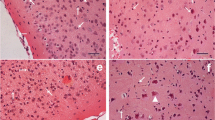

Photomicrograph of HE-stained sections showed intact microstructure of cerebral cortex of juvenile mice from the control group (Fig. 1a). In the low-dose group, microstructure of each layer of cerebral cortex was similar to that of control mice, and remarkable pathological changes were not found. However, in medium-dose group, pia mater encephali slightly divorced from cerebral cortex layer, vacuolar degeneration appeared in part granule cells, hyperemia was observed in blood capillary, and vessel peripheral clearance broadened (Fig. 1b). Microstructural damage of cerebral cortex in juvenile mice exposed to high-dose cadmium was more serious. Pia mater encephali remarkably divorced from cerebral cortex layer, serious hyperemia of blood capillary was observed in pia mater encephali, vessel peripheral clearance broadened, and the numbers of apoptotic cells obviously increased (Fig. 1c). Additionally, a large number of eosinophil leukocyte infiltrated around the blood vessel and vacuolar degeneration also appeared in part granule cells (Fig. 1d).

Effect of cadmium exposure on the microstructure of cerebral cortex of juvenile mice. a Photomicrograph of normal cerebral cortex of juvenile mice. Intact microstructure of cerebral cortex layer. b Photomicrograph of cerebral cortex of juvenile mice exposed medium dose cadmium. Pia mater encephali slightly divorcing from cerebral cortex layer (cross), vacuolar degeneration in part granule cells (triangle), hyperemia of blood capillary (diamond), and broadening vessel peripheral clearance (star). c and d Photomicrograph of cerebral cortex of juvenile mice exposed to high-dose cadmium. c Pia mater encephali of juvenile mice seriously divorcing from cerebral cortex layer (cross), serious hyperemia of blood capillary in pia mater encephali (arrow), broadening vessel peripheral clearance (star) and obviously increasing apoptotic cells (asterisk). d Hyperemia of blood capillary (diamond), a large number of eosinophil leukocyte infiltrating around blood vessel (pound sign), vacuolar degeneration in part granule cells (triangle) and obviously increasing apoptotic cells (asterisk). Magnification: ×400 (a–d). Scale bars a–d 200 nm. There was HE staining